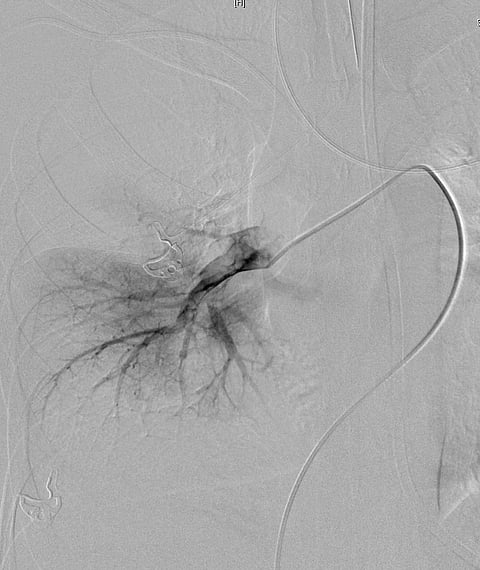

سبق- مكة المكرمة: نجح فريق طبي بمستشفى النور التخصصي بعد عناية الله في إنقاذ حياة شاب عشريني تعرض لجلطة بالشريان الرئوي الرئيس، التي تسببت في انسداد كامل لجميع الشرايين الرئوية.

وقام الفريق الطبي برئاسة الدكتور عبدالحفيظ علوي رئيس قسم الأشعة بالمستشفى بالتدخل العاجل لإزالة الجلطة الكبيرة التي أدت إلى انسداد الشريان الرئيس للرئتين، وذلك باستخدام أحدث التقنيات في الأشعة التداخلية من خلال جهاز خاص يعمل على إذابة وسحب الجلطات من الشريان الرئوي الرئيس عبر القسطرة.

وأوضح الدكتور عبدالحفيظ علوي أن العملية استغرقت ساعة واحدة فقط، وهذا بفضل الله تعالى ثم بفضل الإمكانيات المتوفرة بالمستشفى، حيث إن مثل هذه الحالات كانت تجرى في السابق إما بفتح الشريان بالجراحة ومكوث المريض بالعناية المركزة لعدة أسابيع، أو مكوث المريض لعدة أشهر بالعناية المركزة باستخدام مذيبات الجلطات الرئوية حتى تتحسن حالته.